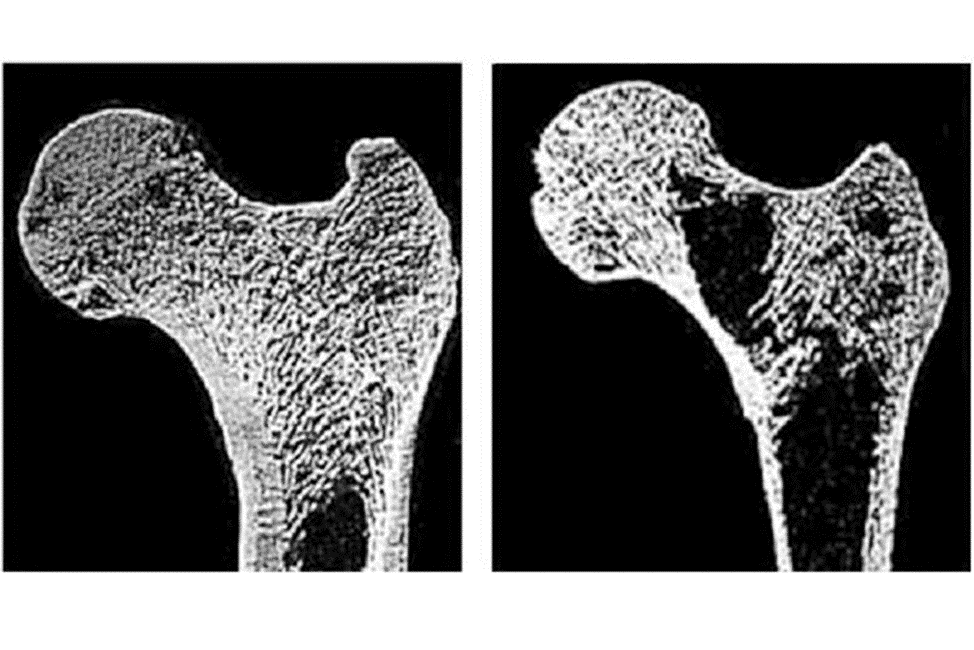

Остеопороз - это хроническое заболевание костей скелета, которое связано с нарушением обмена веществ, проявляется прогрессирующим снижением плотности и нарушением структуры костной ткани и приводит к переломами при минимальной травме (например, при падении с высоты собственного роста или при посадке на стул). Часто бывают переломы позвонков, о которых человек ничего не знает.

3. Дефицит витамина D — главный враг костей и суставов. У 80% мужчин в России — дефицит витамина D. Без него кальций не всасывается, и кости становятся пористыми.

Они иногда становятся легче легкого.